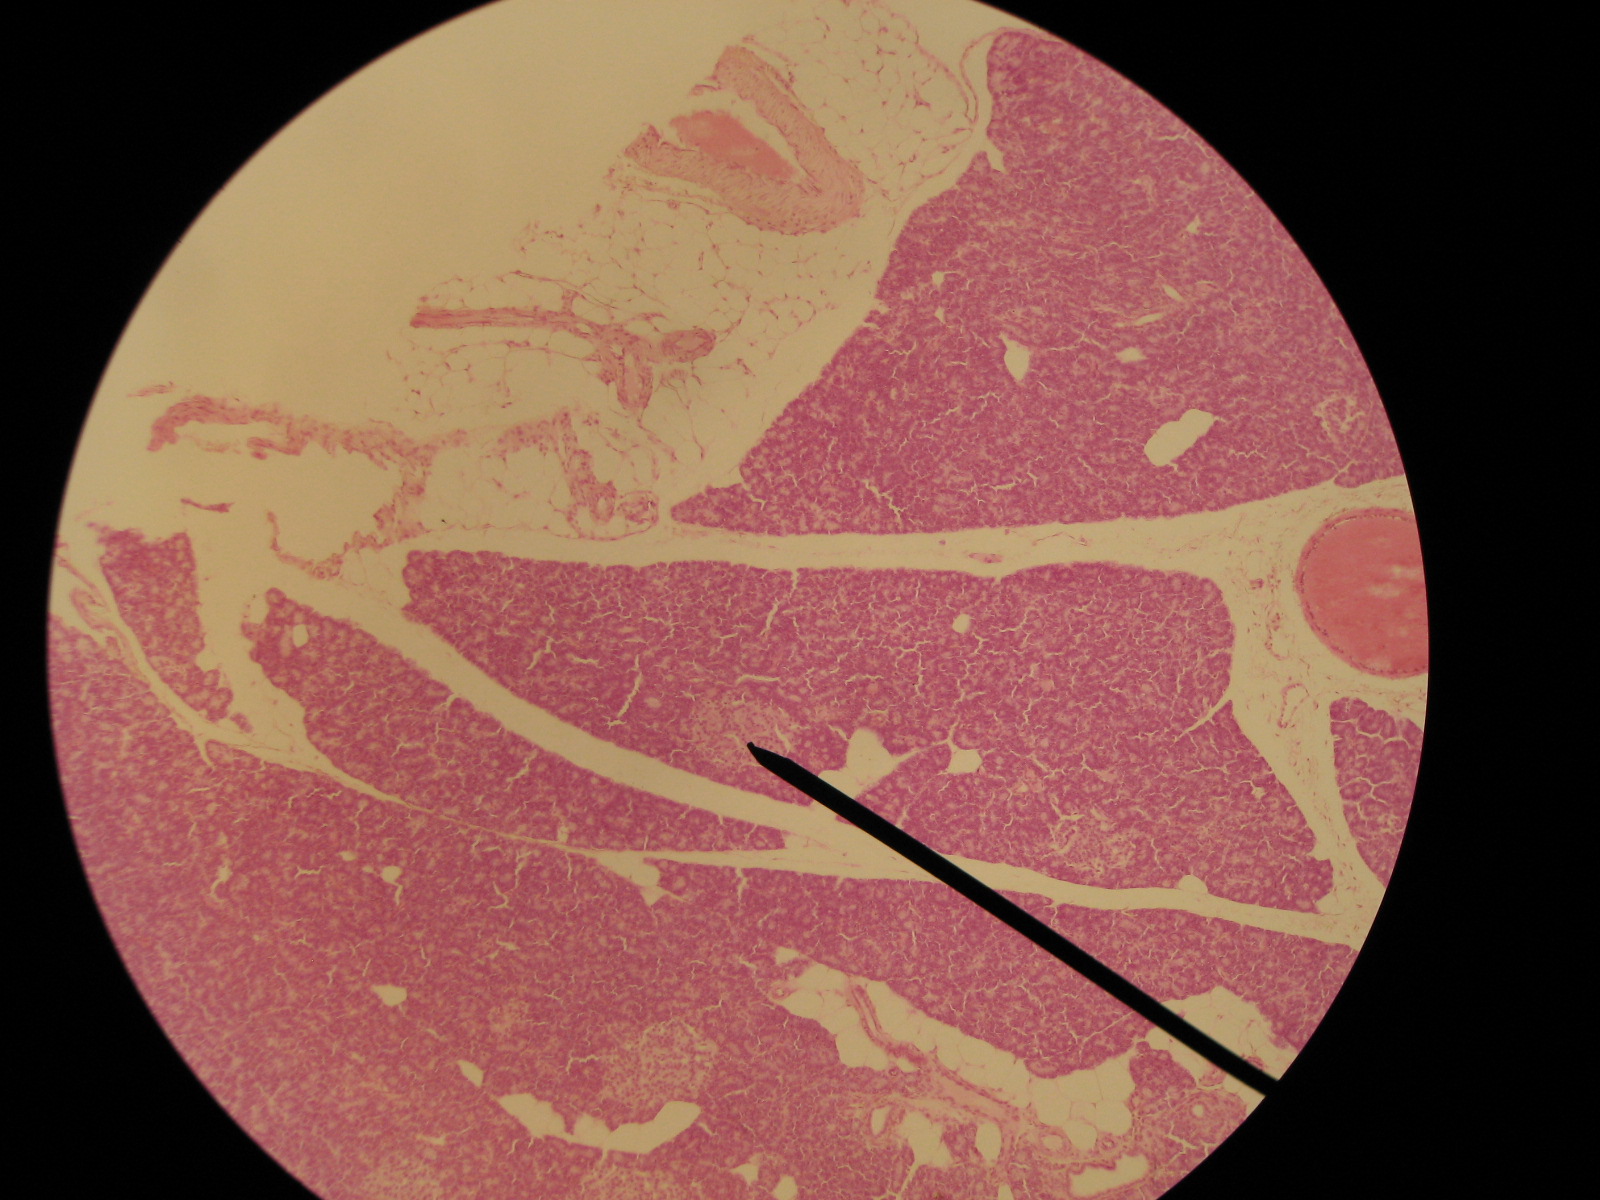

Identify this accessory organ,  | pancreas |